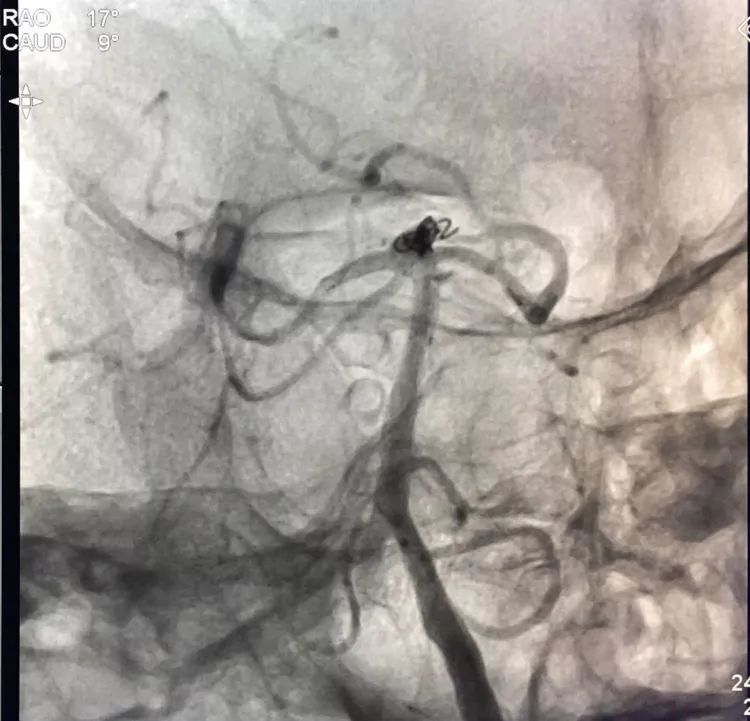

再投入一枚1.5-3的小圈

继续钻入一枚1.5-2的小圈

嗯,完美收官!

回到工作位造影,显示基底动脉顶端动脉瘤完全栓塞,基底动脉顶端四根血管畅通。

术后左椎动脉正位、侧位的造影和蒙片